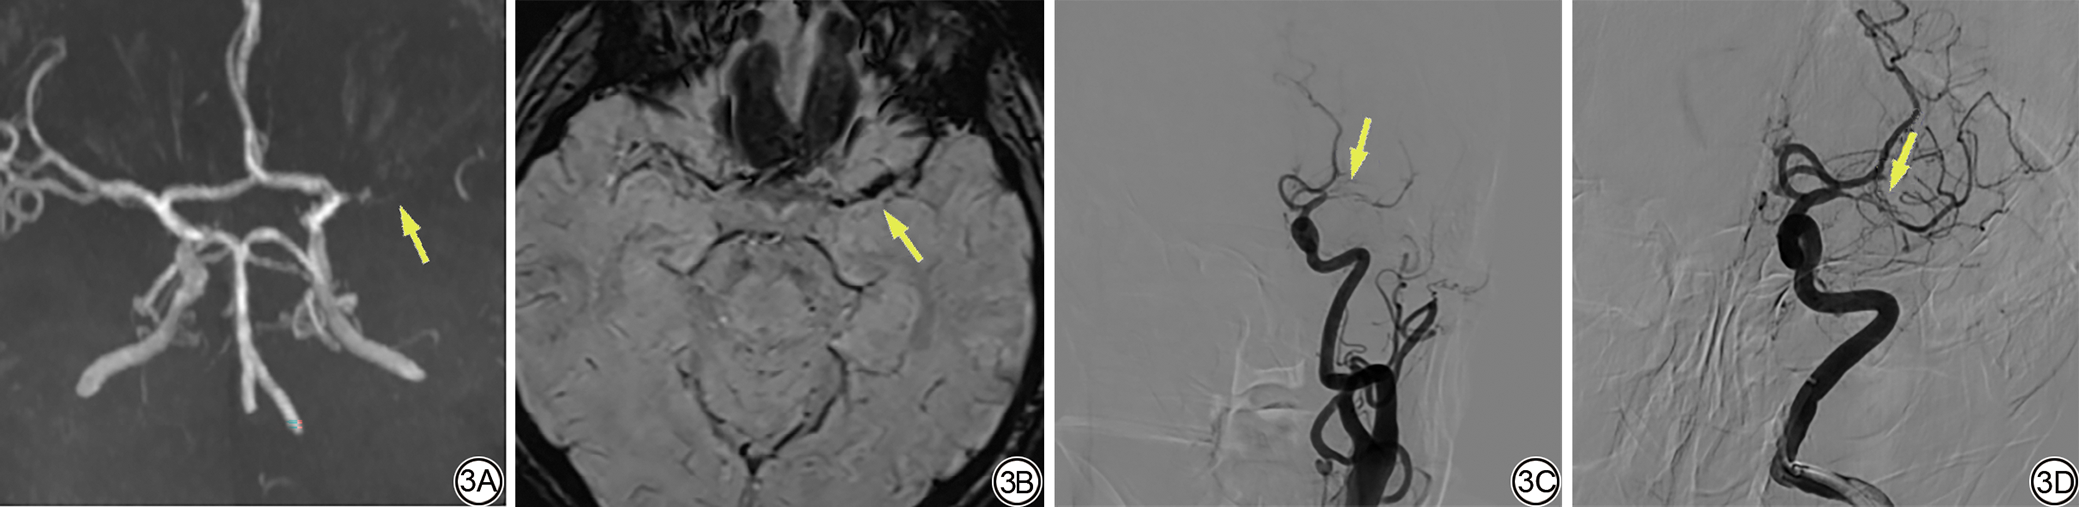

入组患者基线临床特征与成功再通的单因素分析结果见表1。成功再通组SVS宽度大于未成功再通组(图2图3),差异具有统计学意义(P<0.001)。成功再通组与未成功再通组SVS长度差异无统计学意义(P=0.871)。

图3  女,68岁,左侧大脑中动脉M1段供血区脑梗死患者。3A:MRA显示左侧大脑中动脉M1段闭塞(箭);3B:SWI图显示SVS宽度为3.8 mm(箭);3C:DSA显示左侧大脑中动脉M1段闭塞(箭);3D:血管内治疗后显示未成功再通(箭)。MRA:磁共振血管造影;SWI:磁敏感加权成像;SVS:磁敏感血管征;DSA:脑血管造影。

Fig. 3  Female, 68 years old, with cerebral infarction in the M1 segment of the left middle cerebral artery. 3A: MRA shows occlusion of the M1 segment of the left middle cerebral artery (arrow); 3B: The SVS is shown in the SWI graph, with a width of 3.8 mm (arrow); 3C: DSA shows occlusion of the M1 segment of the left middle cerebral artery (arrow); 3D: Endovascular treatment shows no successful recanalization (arrow). MRA: magnetic resonance angiography; SVS: susceptibility vessel sign; SWI: susceptibility weighted imaging; DSA: digital subtraction angiography.